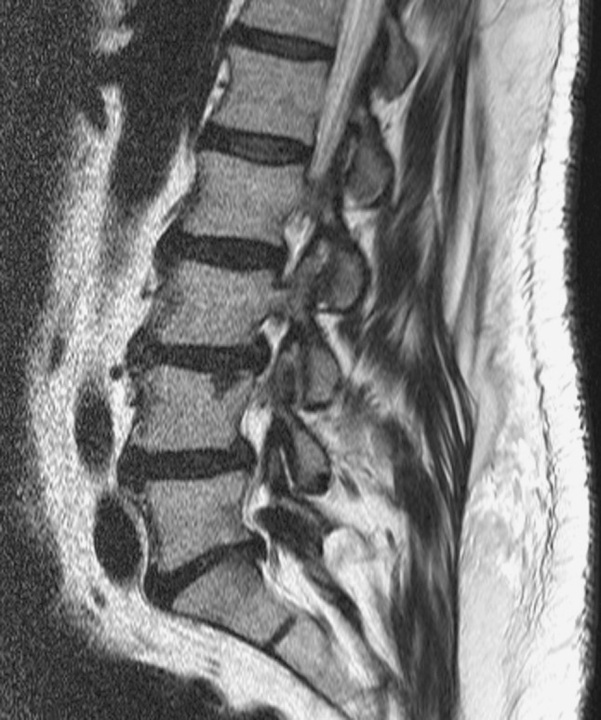

Сагиттальная МРТ, показывающая случайно обнаруженный узел Шморля на уровне L4- позвонка

Лучшим методом визуализации является МРТ. Хотя обычные рентгенограммы могут обнаружить эти поражения, они в основном полезны на поздних стадиях поражения, когда происходит некоторая кальцификация вокруг ГШ..

МРТ - золотой стандарт, потому что

• может выявить острые поражения, что дает более раннюю диагностику и более раннее лечение симптоматических поражений.

• Кроме того, было показано, что МРТ способна различать симптоматические и бессимптомные ГШ по усилению сопутствующего отека практически во всех симптоматических случаях, чего нельзя сделать с помощью обычных рентгенограмм.